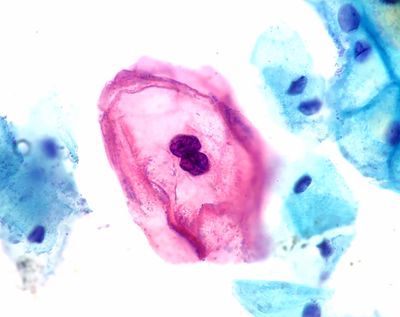

Almost all cervical cancers are caused by HPV infections, most often by two strains which all versions of the HPV vaccine provide excellent protection against. As smoking rates have declined, HPV has also become the cause of more than half of the US’s oropharyngeal (throat) cancers.

“HPV is linked with six different types of cancers, but cervical cancer seems to be the one that people are most aware of,” Sonawane said. "It was first approved for girls and heavily marketed toward girls. Even the packaging was pink.”

Mass HPV vaccination campaigns started in 2006. Cervical cancer most often occurs in the 30s and 40s, so those that were part of the original program are reaching what was once the prime risk age. The good news is that cervical cancer rates among this group are drastically lower than for previous generations, proving the vaccine’s success.

Although cervical cancer is the most common HPV-linked disease, the vaccines are now approved for boys as well. However, vaccination rates have never caught up. The lower awareness of the link to other cancers reflects what pediatricians have reported anecdotally. “People think, ‘Oh, cervical cancer. I don't need to get my boys vaccinated,’” Sonawane said.